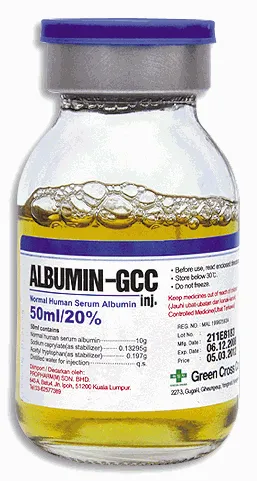

O paciente está congesto? O que realmente ajuda na prática?

O paciente está congesto? O que realmente ajuda na prática?